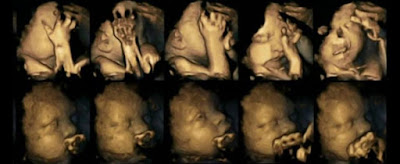

| Reaksi Bayi Dalam Kandungan Seorang Perokok |

Diatas merupakan imbasan imej terhadap kandungan ibu yang merokok semasa hamil. Gambar tersebut, menunjukkan bayi dalam kandungan turut memberi reaksi dengan menutup mata dan mengerutkan wajah selain menyentuh wajah mereka untuk memberi gambaran ketidakselesaan yang dialaminya

Kesan yang sama juga mungkin turut dirasai oleh bayi dalam kandungan apabila ibu mereka menghidu asap rokok daripada si suami ataupun duduk berhampiran dengan perokok lain. Jesteru, kepada ibu bapa yang merokok, disarankan untuk berhenti merokok demi kesihatan janin dalam kandungan.